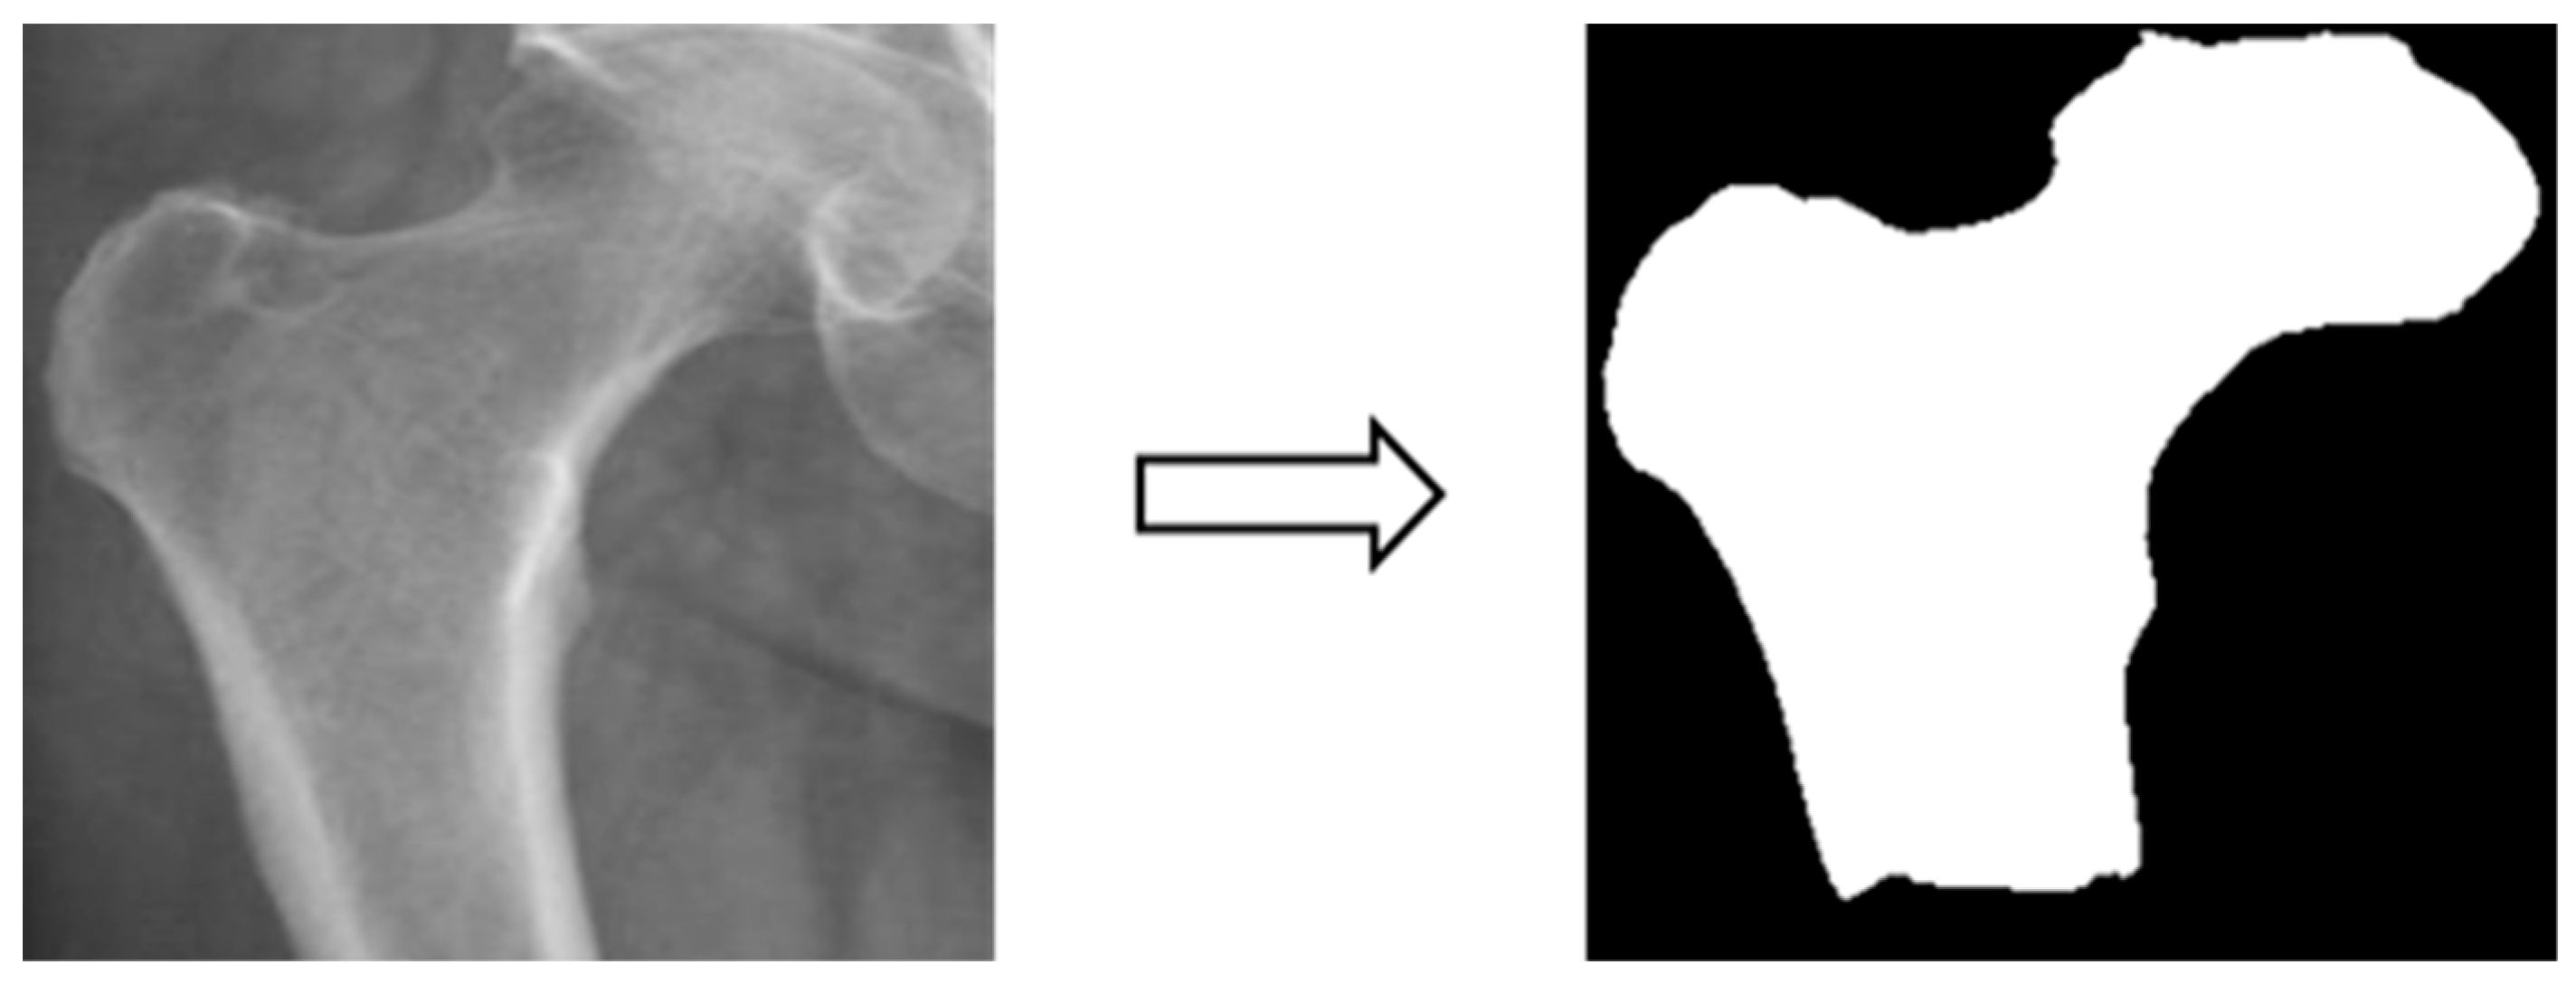

3.3.3. Image matting

Based on the four parts of the image segmentation of the binary image and the original X-ray image together, the original X-ray image only retains the part of the image segmentation as shown in Figure 4; the other non-part of the contour of the background to remove, the image de-behind the hope that it can enhance the accuracy of the classification of the depth of the learning process, and then the image classification will be segmented images and not segmented images will be compared.